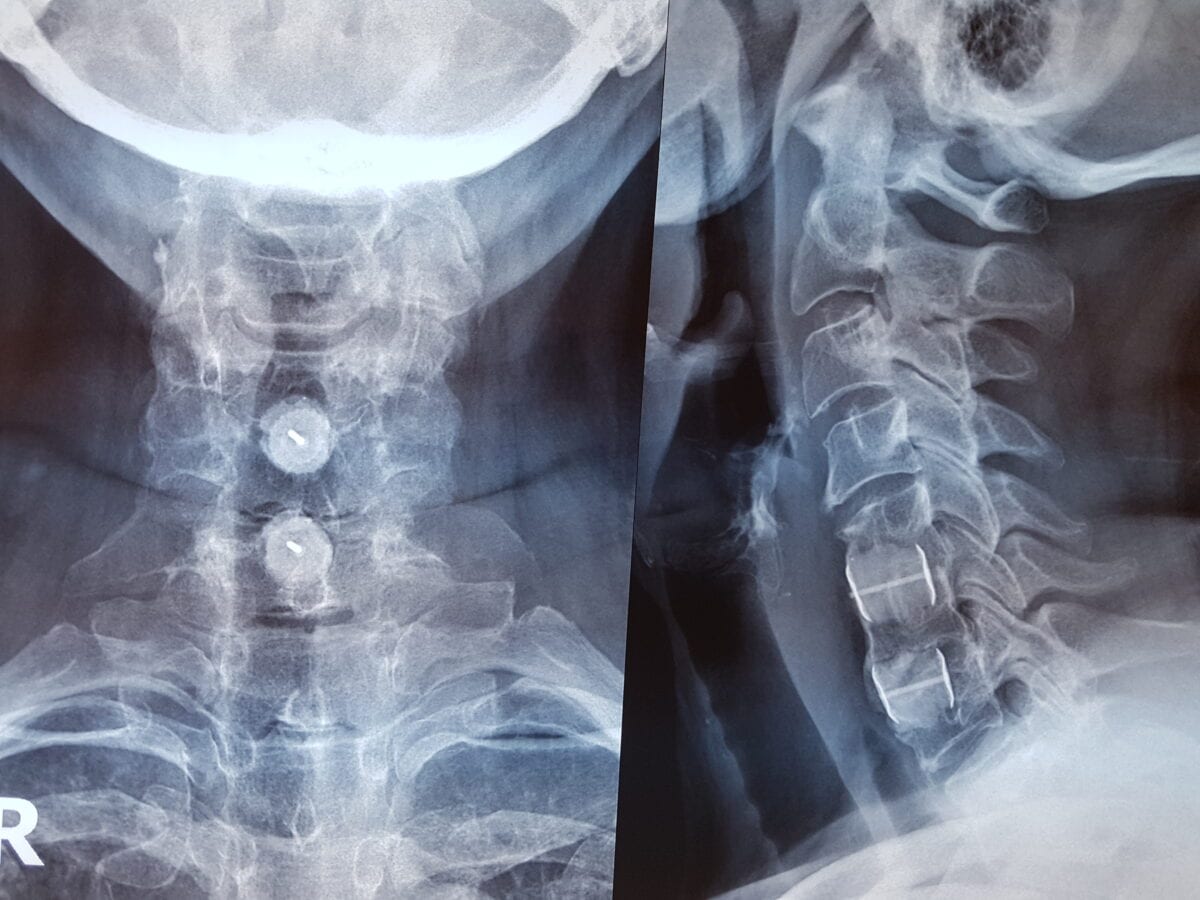

Για να διαγνωσθεί πλήρως η αυχενική σπονδύλωση, πραγματοποιείται κλινική εξέταση και μελέτη του ιατρικού ιστορικού του ασθενούς. Η εκτέλεση απεικονιστικών εξετάσεων, όπως ακτινογραφίες, αξονική και μαγνητική τομογραφία είναι απαραίτητη. Σημαντικό θεωρείται και το ηλεκτρομυογράφημα, ώστε να καθοριστεί η εκφύλιση της αυχενικής μοίρας της σπονδυλικής στήλης.

Σε περιπτώσεις όπου ο ασθενής εξακολουθεί να εμφανίζει συμπτώματα, όπως έντονο πόνο στον αυχένα και τα άνω άκρα, τότε συνίσταται η χειρουργική θεραπεία για την αυχενική σπονδύλωση. Η συνήθης χειρουργική αντιμετώπιση είναι η πρόσθια αυχενική δισκεκτομή και σπονδυλοδεσία.

Πιο συγκεκριμένα, αφού υποβληθεί ο ασθενής σε γενική αναισθησία, ο ιατρός αφαιρεί τον πάσχοντα δίσκο, αντικαθιστώντας τον με ένα κομμάτι οστού. Το οστό αυτό προέρχεται από την πύελο (λεκάνη) του ασθενούς ή από τράπεζα οστού.

Με την τεχνική αυτή, αφενός αφαιρούνται τα οστεόφυτα και ο δίσκος που ασκούν πίεση στον νωτιαίο μυελό και αφετέρου ακινητοποιείται το μεσοσπονδύλιο κενό με την τοποθέτηση των μοσχευμάτων και της πλάκας.